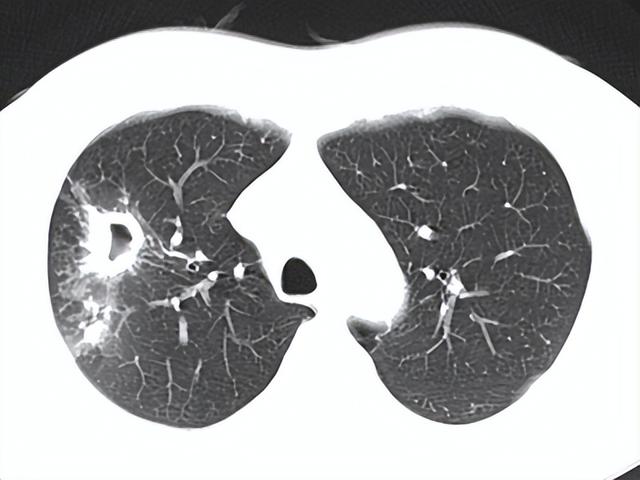

近日,首都医科大学附属北京胸科医院结核科初乃惠主任讲述了一个真实的病例:一个17岁男孩学校体检时发现肺部阴影,经相关检查后确诊为肺结核。但青春期的孩子似乎总有他的执拗,男孩怎么也不接受治疗,他振振有词地说:“我既没有咳嗽又没有痰,也没有其他什么症状,你就说我得了肺结核,我凭什么听你的去治病!”

对于PPD试验是阳性和强阳性的人群,如果有结核患者密切接触史,建议到医院行胸片或CT检查。如果胸片或CT都没问题则只需动态观察,不需要特殊处理。如果胸片或CT有问题,就需要进一步查痰明确诊断。